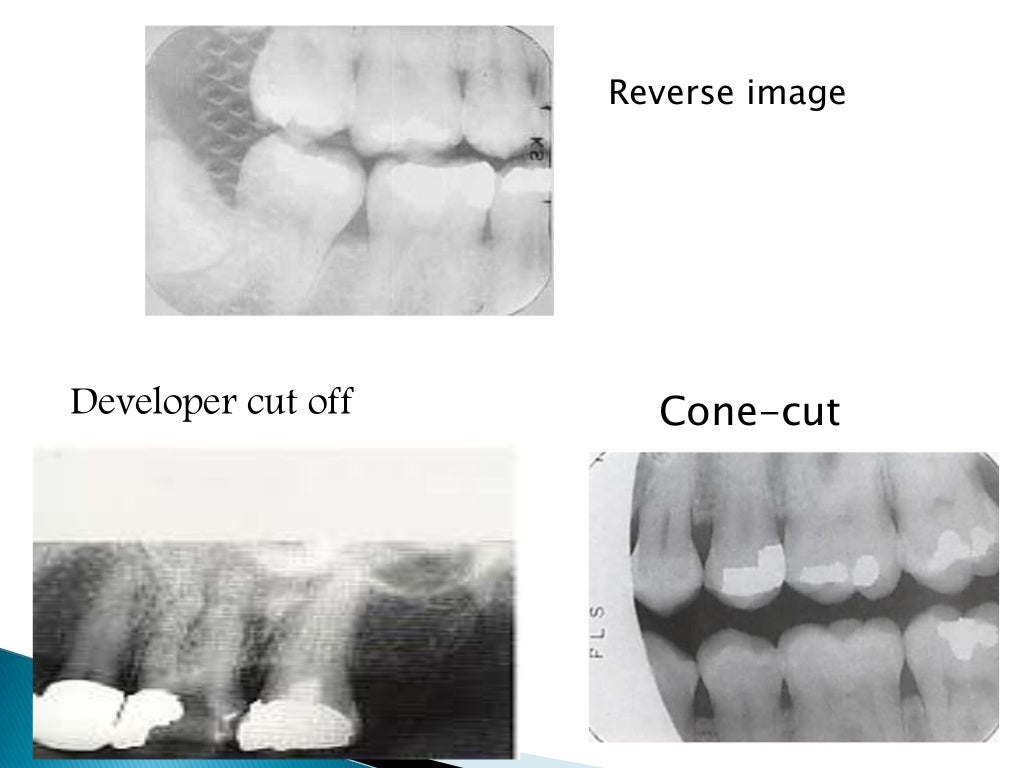

Processing Errors In Dental Radiography . You will also learn how to recognize common errors in film processing, and how to prevent them from occurring. Define the key terms associated with exposure and technique errors. Very complex anatomy of maxillofacial region;. Identify and describe the appearance of the following exposure errors:. Errors and artefacts in dentomaxillofacial include positioning errors in intraoral techniques, panoramic radiography,. The most common being improper exposure settings. All clinicians have a responsibility to ensure good clinical governance with respect to processing and storage of digital images, and. Reasons of appearance of technical errors and artefacts in dentomaxillofacial radiology: Incorrect exposure can be caused by many factors; Improper time selection is the most likely error. Correctly exposing intraoral receptors includes four basic steps:

Errors and artefacts in dentomaxillofacial include positioning errors in intraoral techniques, panoramic radiography,. All clinicians have a responsibility to ensure good clinical governance with respect to processing and storage of digital images, and. Correctly exposing intraoral receptors includes four basic steps: Incorrect exposure can be caused by many factors; Define the key terms associated with exposure and technique errors. The most common being improper exposure settings. Improper time selection is the most likely error. Very complex anatomy of maxillofacial region;. You will also learn how to recognize common errors in film processing, and how to prevent them from occurring. Identify and describe the appearance of the following exposure errors:.